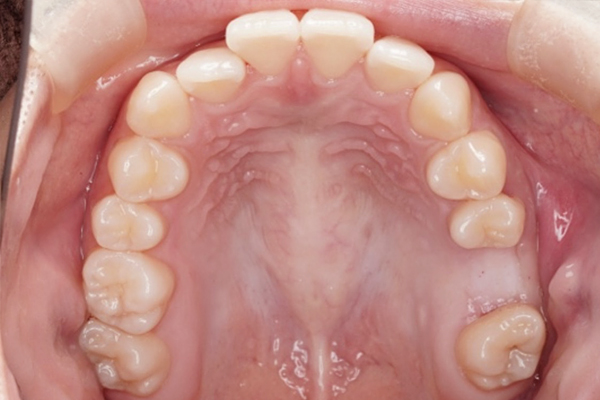

歯槽堤温存術

(リッジプリザベーション)後4週間

歯槽堤温存術の症例

歯を抜歯し、骨補填剤をいれ、骨補填剤が出てこないようにメンブレンで閉じました。大きな感染もなく歯肉の状態も良好です。

これから、5ヶ月前後治癒期間を待ちその後インプラント治療を行なっていきます。